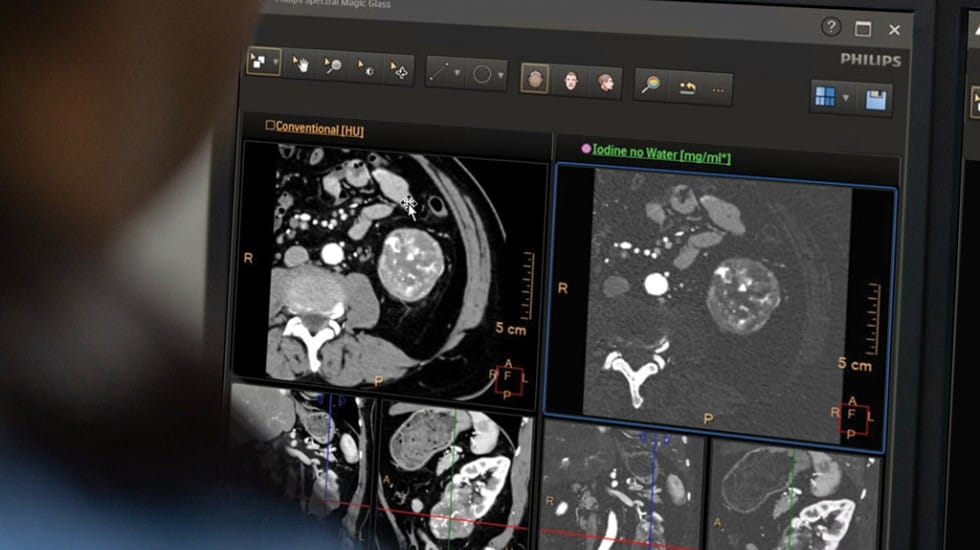

このたびフィリップスが発売する「Verida」は、CT撮影から画像再構成に至る画像取得(イメージングチェーン)の工程にAIを統合した、世界初のディテクターベース・マルチエナジースペクトラルCTです。Veridaは、従来のCT検査と同一のワークフローで、1回の撮影から高精細な通常画像と豊富なスペクトラル情報を同時に取得することが可能です。これにより、検査効率の向上と再撮影の低減を通じて、医療従事者の業務負担軽減とワークフロー改善をサポートします。Veridaの導入により、診断精度の向上とともに、放射線科を中心とした医療現場全体の生産性向上が期待されます。

1. 世界初AI搭載ディテクターベース・マルチエナジースペクトラルCT Veridaは、フィリップスが先駆的に開発・臨床普及を進めてきたディテクターベース・スペクトラルCT技術に、先進的なAI技術を統合した世界初のCTシステムです。撮影、検出、画像再構成といった一連のCT画像取得の工程にAIを活用することで、システムノイズを低減し、高精細で安定した画質を実現します。また、通常のCT検査と同一のワークフローで、1回の撮影から高品質な通常画像と豊富なスペクトラル情報を同時に取得することが可能です。これにより、検査条件の追加設定や撮り直しを必要とせず、診断に有用な情報のより迅速かつ確実な提供に寄与し、診断の信頼性向上に貢献します。 2. 高速画像再構成による検査スループット向上と業務効率化 Veridaは、最大毎秒145枚※ 3の高速画像再構成を可能にし、検査終了後30秒以内※3に検査全体の画像を自動的に表示できます。これにより、検査後の待機時間や読影準備に要する時間を大幅に短縮し、放射線科における検査スループットの向上を支援します。 検査件数が増加する一方で人材不足が課題となる医療現場において、Veridaは限られたスタッフでも効率的な検査運用を可能にし、1日あたりの検査対応数の増加に寄与します。結果として、医療従事者の業務負担を軽減するとともに、患者の待ち時間短縮など、医療サービス全体の質向上が期待されます。 3. 被ばく低減と持続可能な医療体制の構築を支援 Veridaは、マルチパスAI独自方式※ 4を採用した画像再構成技術により、画質を維持しながら被ばく線量の低減が期待される設計となっています。診断に必要な情報を効率的に引き出すことで、不必要な再撮影の抑制にもつながり、患者にとってより安全な検査環境の提供に貢献します。 さらに、システムの効率化によりエネルギー消費の削減も見込まれ、医療機関における環境負荷低減や運用コストの最適化を支援します。Veridaは、高度な診断性能と業務効率化を両立させることで、医療従事者・患者・医療機関のすべてに配慮した、持続可能な医療提供体制の構築に貢献します。